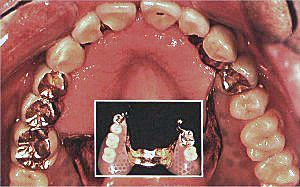

Die Teleskop - Prothese bevorzugt die komfortablere Befestigung mit Hilfe von Teleskopkronen. Dabei werden die entsprechenden Zähne zunächst mit Unter - Kronen versorgt und geschützt. Die Ober - Kronen (Teleskope) dienen zur Befestigung des Zahnersatzes und sind zusammen mit diesen herausnehmbar. Die Teleskop - Prothese zeichnet sich durch ihre exakte Passung und völlig unkomplizierte Handhabung aus. Sie gewährleistet ein absolut sicheres Kaugefühl ohne Fremdkörperempfinden und ist optisch unauffällig.